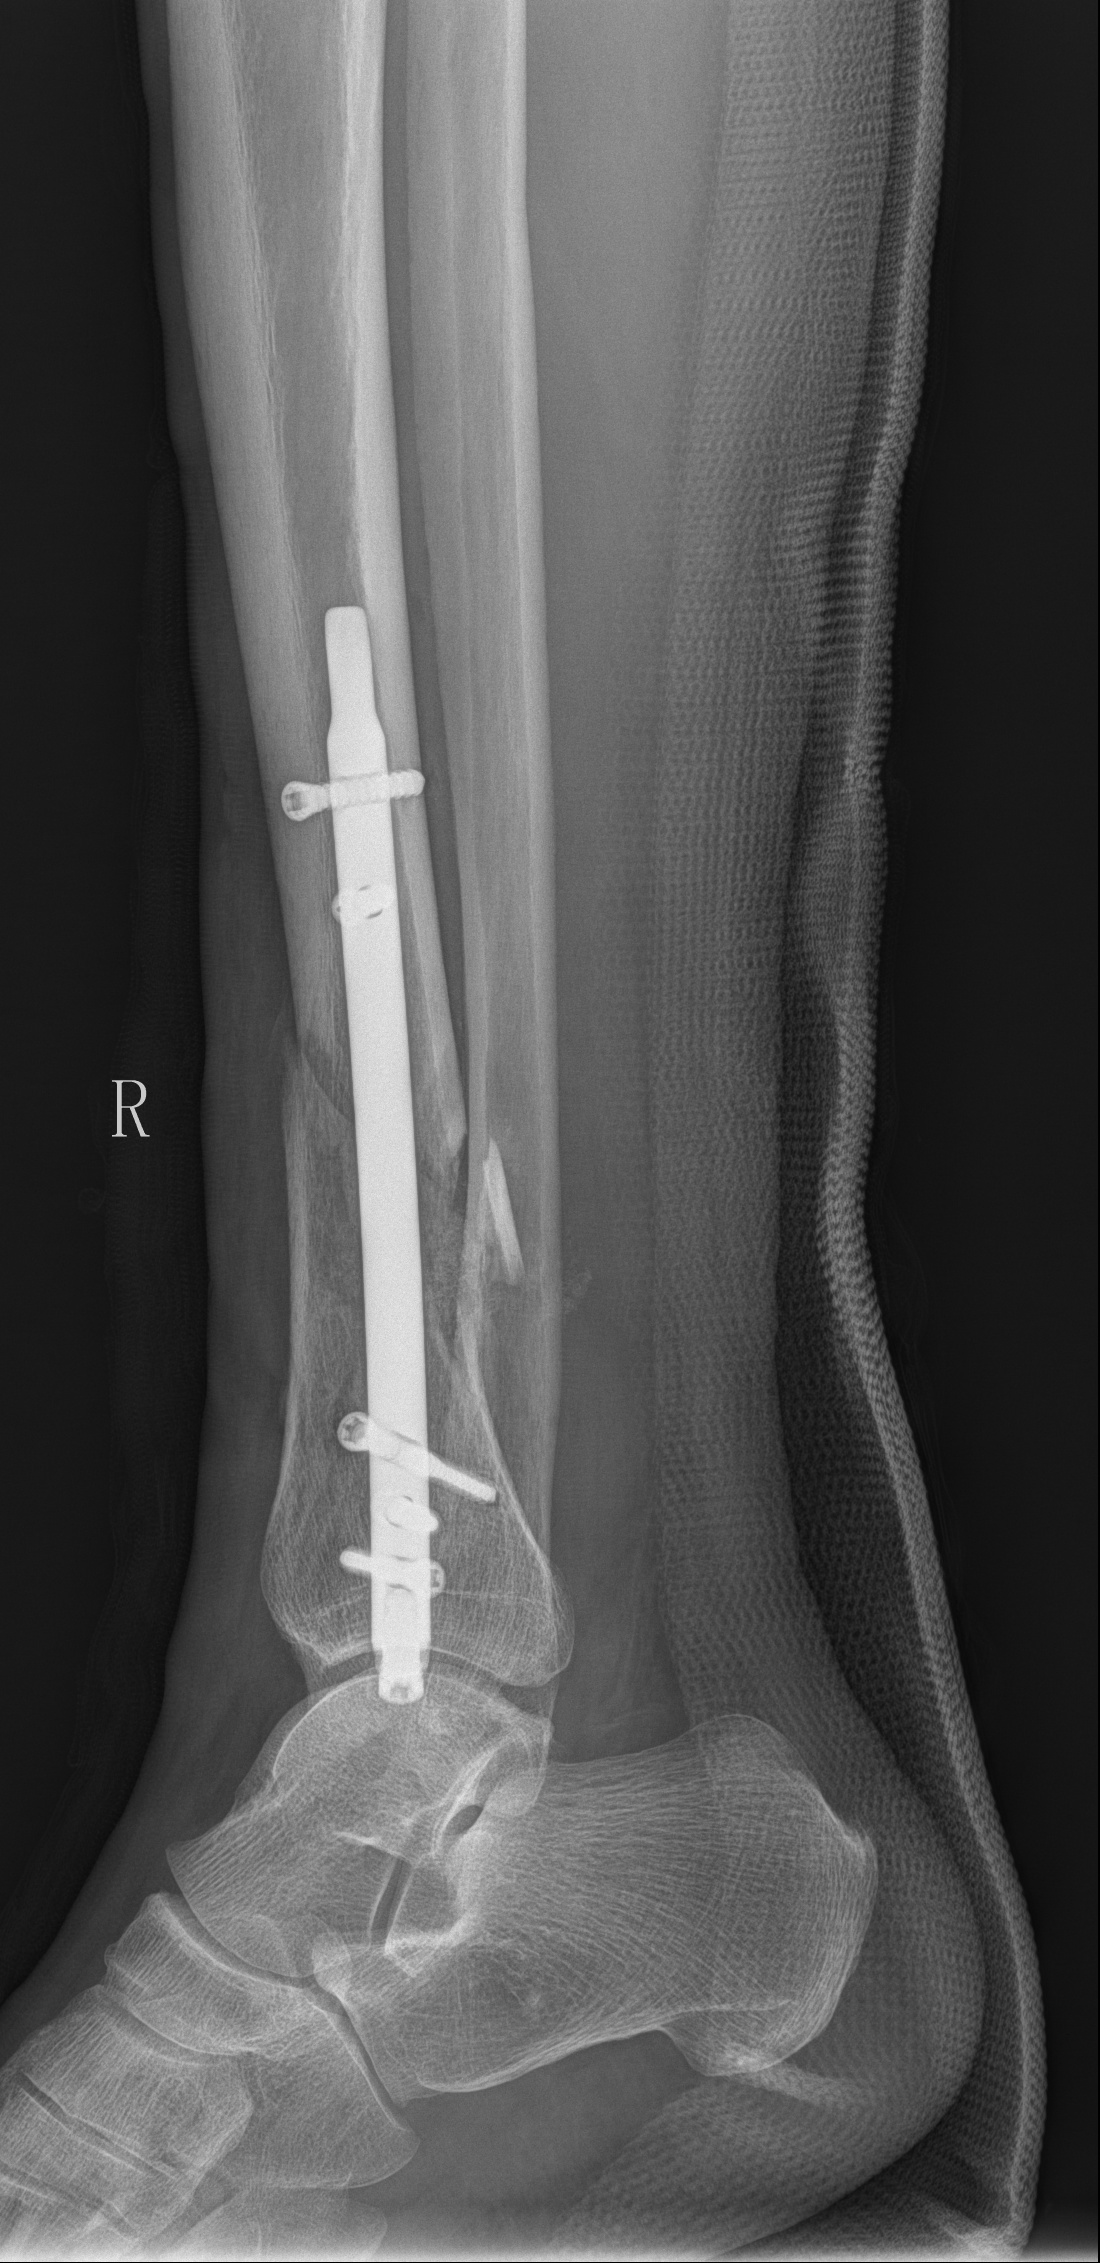

DTN术后复查右胫腓骨正侧位

近日,金瓶梅电影 创伤骨科医师团队成功完成了一例右胫骨远端开放性骨折闭合复位逆行倒打髓内钉内固定(DTN)手术,该手术是江西省内第一台胫骨逆行髓内钉手术,具有突破性意义。相比于传统手术方式,DTN具有手术创伤小,术中出血量少,切口小,手术时间短,内固定稳固,术后恢复快等优点,能迅速帮助患者减少病痛,快速进行康复。

胫骨远端骨折因其解剖结构的特殊性,容易出现软组织并发症。胫骨远端骨折可选用切开复位钢板固定、MIPPO钢板固定、胫骨顺行髓内钉固定、胫骨逆行髓内钉技术及外固定。其中切开复位及MIPPO技术手术切口较大,切口处缺乏软组织覆盖,容易出现切口感染。且钢板为偏心型固定,力学稳定性不如髓内钉的中心型固定。顺行髓内钉因骨折线位置较低远端锁钉把持力不足,同时有诱发膝前疼痛的可能。而胫骨逆行髓内钉技术作为国内逐渐发展起来的新技术,在处理胫骨远端骨折时具有软组织损伤小、复位及固定简易等优势,十分适合本患者。

胫骨远端髓内钉作为一种新型的胫骨带锁髓内钉内固定系统,是髓内钉系统的新成员,可以弥补顺行髓内钉的不足,其主要适应症为闭合性和开放性胫骨远端骨折或小腿远端五分之一骨折和干骺端骨折(AO/OTA43.A1/A2和A3)。或者是胫骨远端骨折,简单涉及到踝关节(AO/OTA43.C1、C2)。胫骨远端逆行髓内钉操作简单,切口更小,对骨质造成的创伤小,降低了对软组织的激惹,可以缩短住院时间及康复时间,符合快速康复ERAS理念。该技术在江西的首次应用为创伤骨科在骨科微创治疗上再添利器。